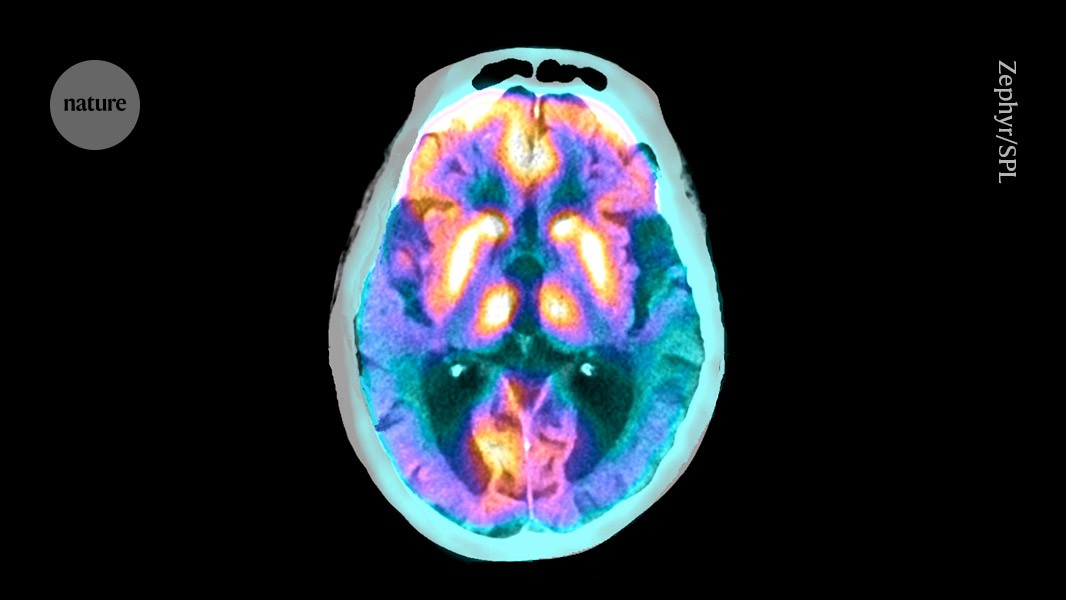

Tau proteins build up in part of the brain of people with Alzheimer’s disease.Credit: Zephyr/SPL